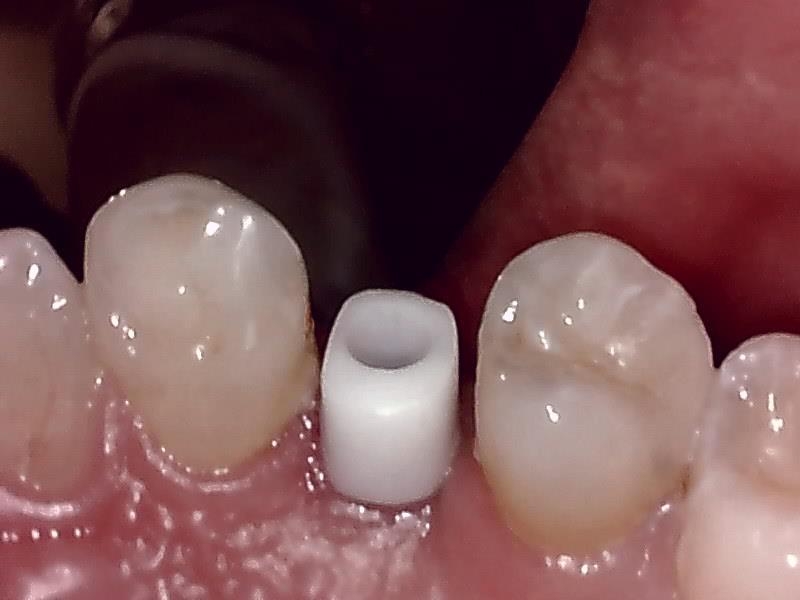

アバットメント装着 (左上)

(ジルコニアアバットメント)

インプラントの上部構造 (左上)

(ジルコニアセラミッククラウン)

歯肉の整形 (左上)とても綺麗な良い歯肉の状態です。